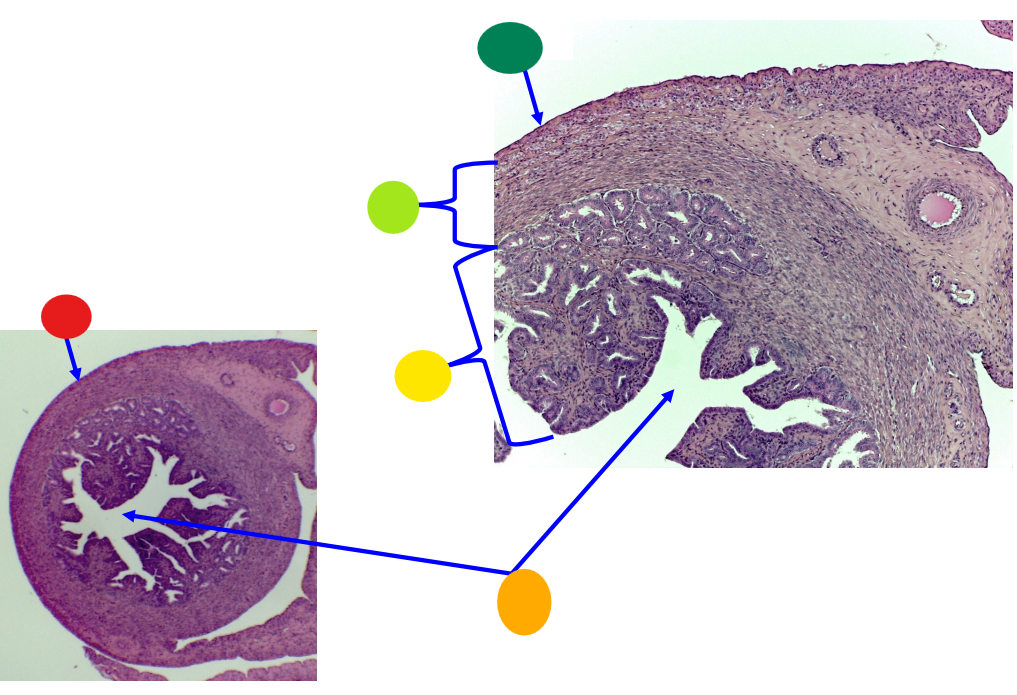

red

primary oocyte

orange

zona pellucida

yellow

granulosa cells

light green

developing thecal cells

What is this

secondary follicle

red

granulosa cells

orange

primary or secondary oocyte

yellow

oocyte nucleus

light green

zona pellucida

dark green

cumulus oophorus

light blue

antrum

dark blue

thecal cells

what is this

tertiary follicle